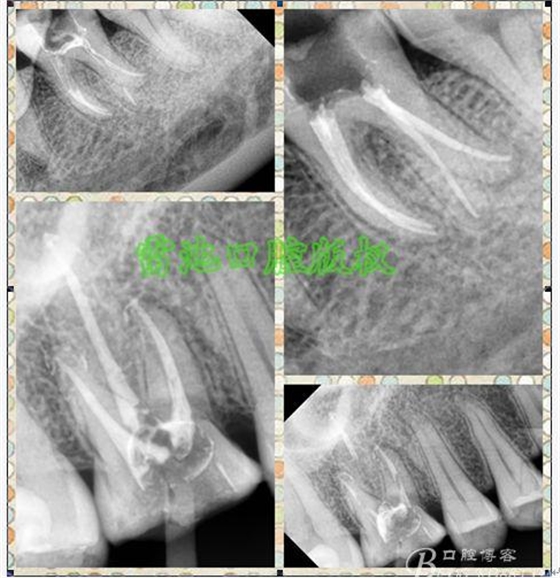

E、X線影像學(xué)的檢查研判能力:這點(diǎn)不需要強(qiáng)調(diào)太多,對(duì)于普通的非CBCT的二維影像對(duì)醫(yī)生讀片能力有一定的要求,有個(gè)逐步提高的過(guò)程,非一蹴而就,需要學(xué)會(huì)把二維的X線影像與三維的解剖結(jié)構(gòu)進(jìn)行良好的對(duì)應(yīng)結(jié)合,對(duì)于某些鈣化的髓室底,應(yīng)通過(guò)想象把根管口的分布、根管的走向以及各種變化通過(guò)想象投射到對(duì)應(yīng)的髓室底上;

F、其它找尋根管的特殊方法:包括染色法(使用赤藻紅或亞甲基藍(lán)染色后,通過(guò)聚合作用或冷光燈透照牙齒,并配合使用尖銳的根管口探針輕輕探查)、溝槽法(選擇合適超聲工作尖,在髓底懷疑根管口出現(xiàn)的特定位置切割一條淺溝,清洗吹干后通過(guò)放大設(shè)備觀察,一般溝底的牙髓組織呈白色,此法對(duì)找尋MB2非常有效)、以及發(fā)泡實(shí)驗(yàn)等等。

G:找尋MB2的問(wèn)題:

1、查閱各種文獻(xiàn),MB2的發(fā)生率在52-96%之間,治療時(shí)遺漏是上頜磨牙根管治療失敗的主因,2、一般位于MB1根管口與腭根管口方向的0.5-5mm范圍內(nèi),而大多數(shù)都位于MB舌側(cè)的1-3mm處,其中2mm以內(nèi)占85.7%,3、MB1-P根管口連線與MB1-MB2根管口的連線夾角大部分(74.3%)在30度以內(nèi);4、MB2的尋找大部分需要去除相應(yīng)部位的牙本質(zhì);5、當(dāng)找到的MB根管口呈“長(zhǎng)線型”且有深色凹線向舌側(cè),或者找到的MB根管口明顯偏頰多提示有MB2的可能;6、DOM(牙科手術(shù)顯微鏡)的使用有助于找尋MB2;